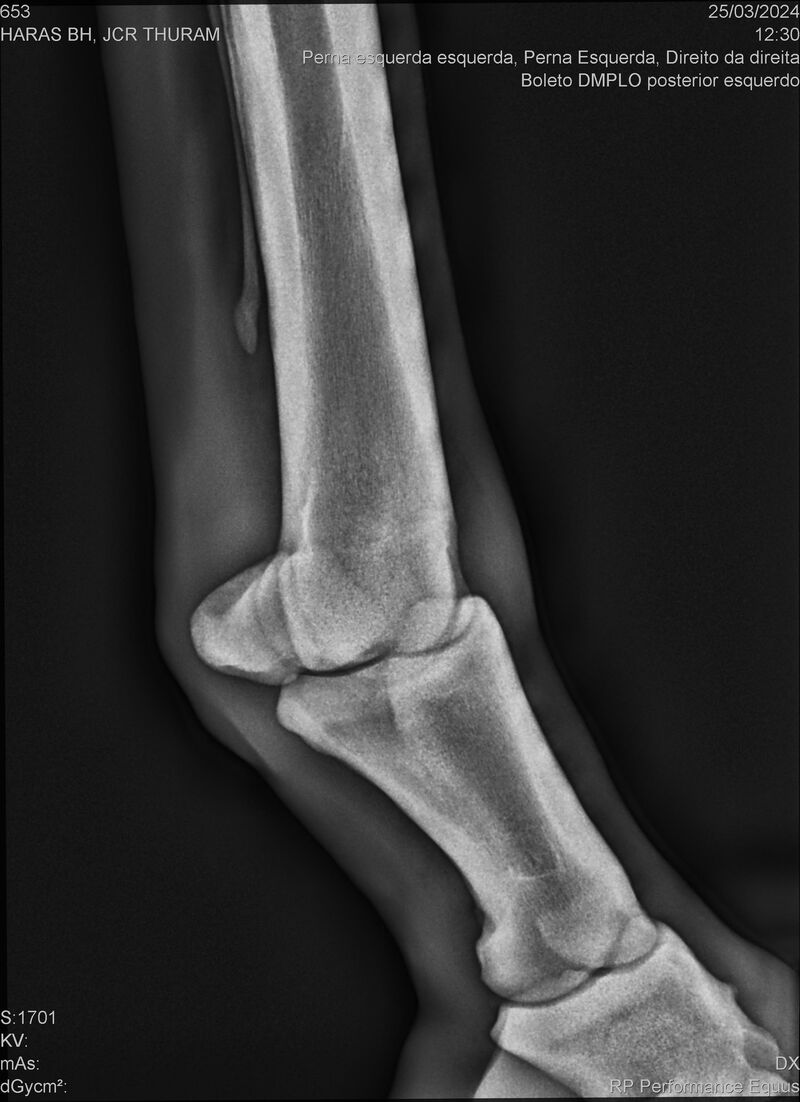

JCR THURAM

Raça: BRASILEIRO DE HIPISMO

Sexo: CASTRADO - CASTRADO

Nascimento: 10/01/2021

Registro: 27531-BH

Vend.: HARAS BH